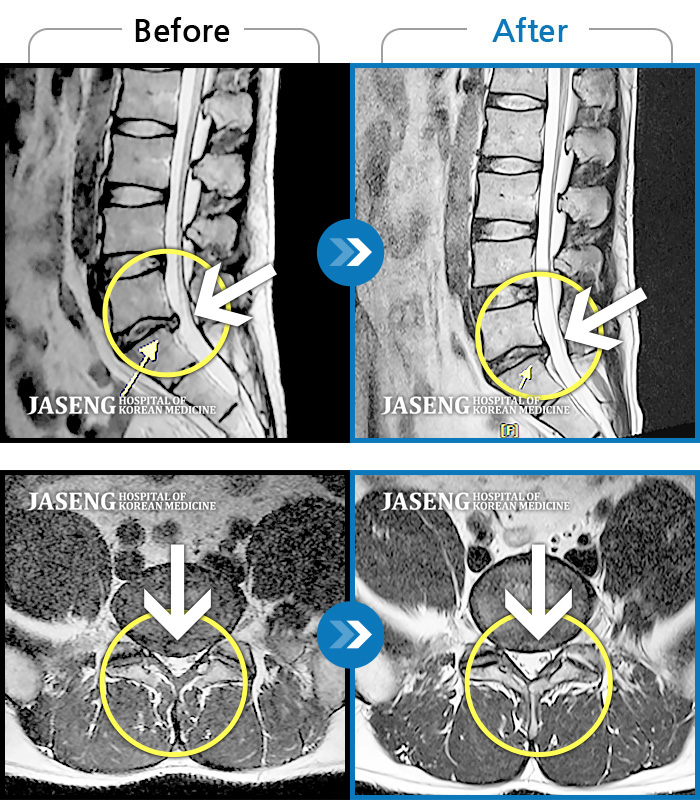

허리디스크

도움받은 사례

광주 · 장영우 원장

좌측 허리 통증으로 허리를 반듯이 펴고 서있기 힘들어 내원하셨습니다.

촬영시기

2024.08.12 ~ 2025.02.26

2025.03.07